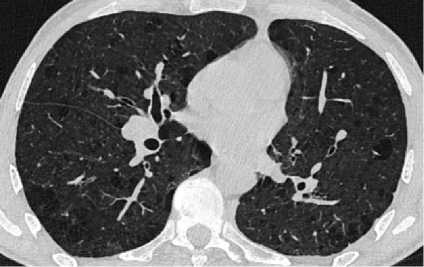

При проведении МСКТ ОГК-В S1 и S2 левого лёгкого субплеврально определяется воздушная полость неправильной формы с толстыми неровными стенками, до 3,5 см в диаметре, небольшим количеством патологического содержимого вдоль стенок. Вдоль заднего контура полости определяется крупная перифокальная зона консолидации, частично сливающаяся со стенкой полости, содержащая в толще единичные мелкие воздушные полости и единичные мелкие кальцинаты. К полости подходят отдельные субсегментарные бронхи, заполненные патологическим содержимым. В апикальных отделах S1 правого лёгкого, субплеврально определяются участки консолидации, с видимыми просветами субсегментарных бронхов – соответствует воспалительным изменениям. В обоих лёгких, в том числе вдоль междолевой плевры, определяются многочисленные мелкие очаги. Отмечаются выраженные эмфизематозные изменения обоих лёгких в виде парасептальной и буллёзной эмфиземы (рис. 1).

Рисунок 1. Аксиальные срезы КТ органов грудной клетки, легочное окно: а – S1 и S2 левого лёгкого, субплеврально определяется воздушная полость неправильной формы с толстыми неровными стенками; б – в обоих лёгких определяются многочисленные мелкие очаги, выраженные эмфизематозные изменения обоих лёгких в виде эмфиземы

Figure 1. Axial CT scans of the chest organs, pulmonary window: a – S1 and S2 of the left lung, an irregularly shaped air cavity with thick uneven walls is determined subpleurally; б – numerous small foci are detected in both lungs, pronounced emphysematous changes in both lungs in the form of emphysema